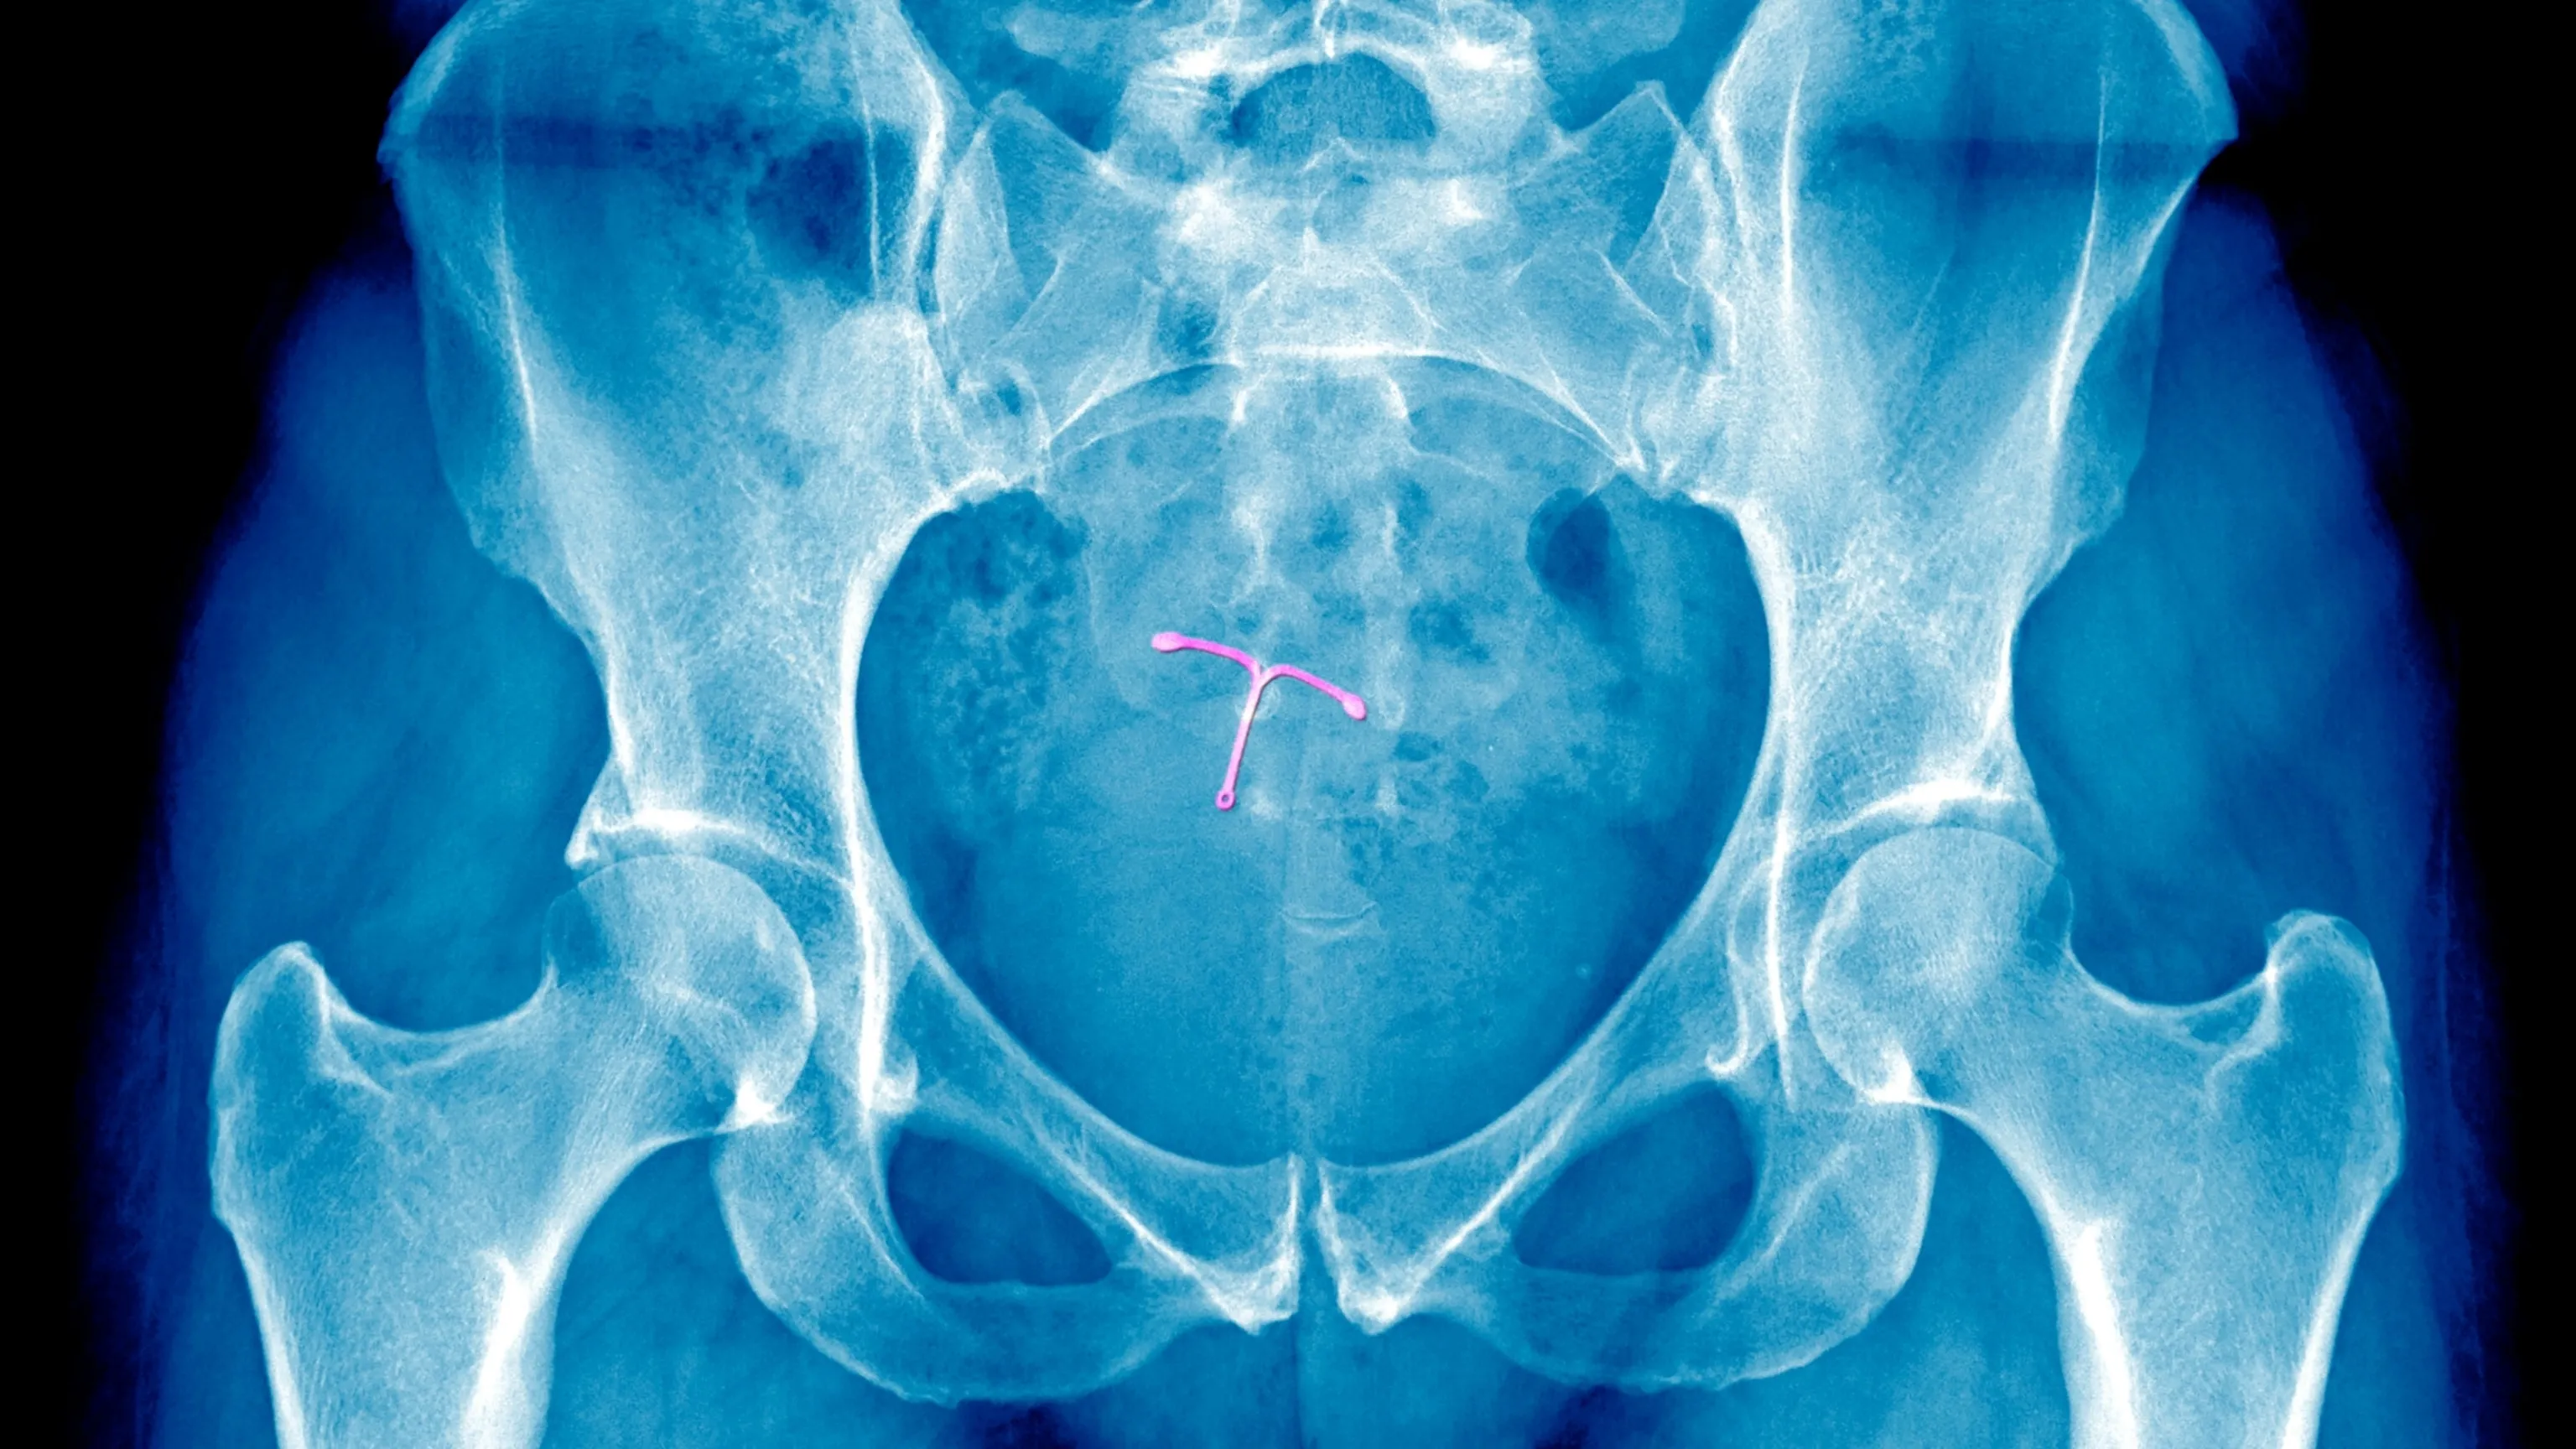

In recent years, women's pain management has seen significant changes as healthcare providers recognize the need to take it more seriously. New initiatives focus on enhancing women's gynecologic procedures, emphasizing the importance of reducing pain. This shift is crucial for women's health and well-being, fostering improved patient experiences.